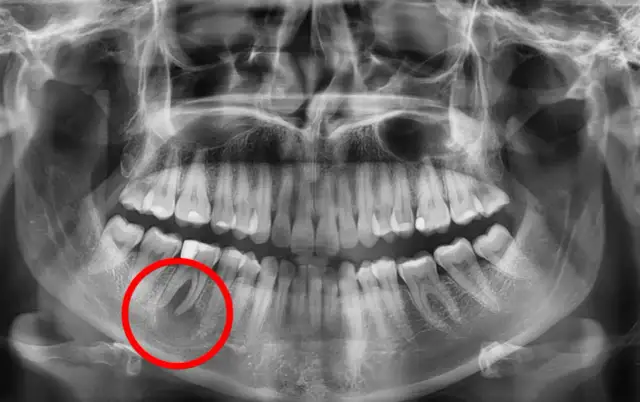

Torbiel pod zębem - Objawy, leczenie, kiedy pilnie do dentysty?

Torbiel pod zębem - dowiedz się, czym jest, jakie daje objawy i powikłania. Sprawdź, kiedy boli, jak diagnozować i leczyć, by uniknąć zagrożeń. Czytaj!

Torbiel na zębie - Jak ją rozpoznać i czy zawsze trzeba ją usuwać?

Torbiel na zębie często nie daje objawów, a niszczy kość. Dowiedz się, jak ją rozpoznać i jak wygląda skuteczne leczenie. Sprawdź porady na Szwedental.pl!